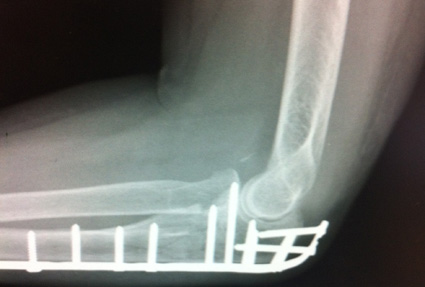

The surgeon showed her the before and after x-rays on his screen and she took a couple of photos with her iPhone. That’s certainly an impressive array of metal in the arm! Does she now qualify as a Cyberwoman?